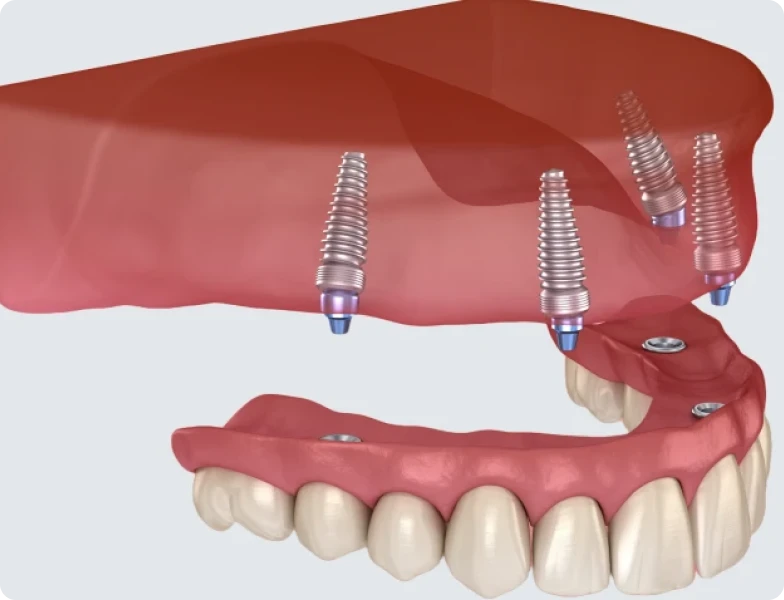

La prothèse amovible stabilisée sur implants

Cette prothèse se clipse sur les implants grâce à des attaches spécifiques. Ce type de prothèse se retire chaque jour pour le nettoyage, tout en assurant une excellente stabilité pendant la journée.

Recherchée pour son équilibre entre confort et simplicité d’entretien, cette solution convient particulièrement aux patients édentés complets. Elle s’avère notamment adaptée à la mâchoire inférieure, où les prothèses traditionnelles peuvent présenter une tenue moins fiable.

Deux à quatre implants suffisent en général pour assurer un bon ancrage. Ce système permet de limiter les frottements sur la gencive et d’améliorer le confort masticatoire.

Une fois les implants intégrés, la prothèse peut être réalisée et mise en place. Pour une prothèse fixe, un pilier est vissé sur chaque implant, puis la structure prothétique est fixée. Pour une prothèse amovible, des attaches de rétention sont placées pour permettre l’ancrage.